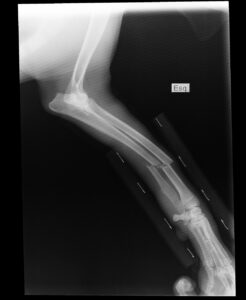

• Barn- och skelettröntgen

broken arm, x-ray, of the cinnamon of, english pointer, broken arm, broken arm, broken arm, broken arm, broken arm, x-ray, x-ray, x-ray, x-ray

Barn- och skelettröntgen

Konrad Röntgens hand

Enheten för Barn- och skelettröntgen är en del av verksamhetsområde Bild och Funktion vid Skånes universitetssjukhus i Lund. Här utför vi radiologiska undersökningar med särskild inriktning mot barn och rörelseapparaten. Med hög specialistkompetens, ett tryggt bemötande och modern utrustning säkerställer vi noggrann diagnostik anpassad efter varje patients behov.